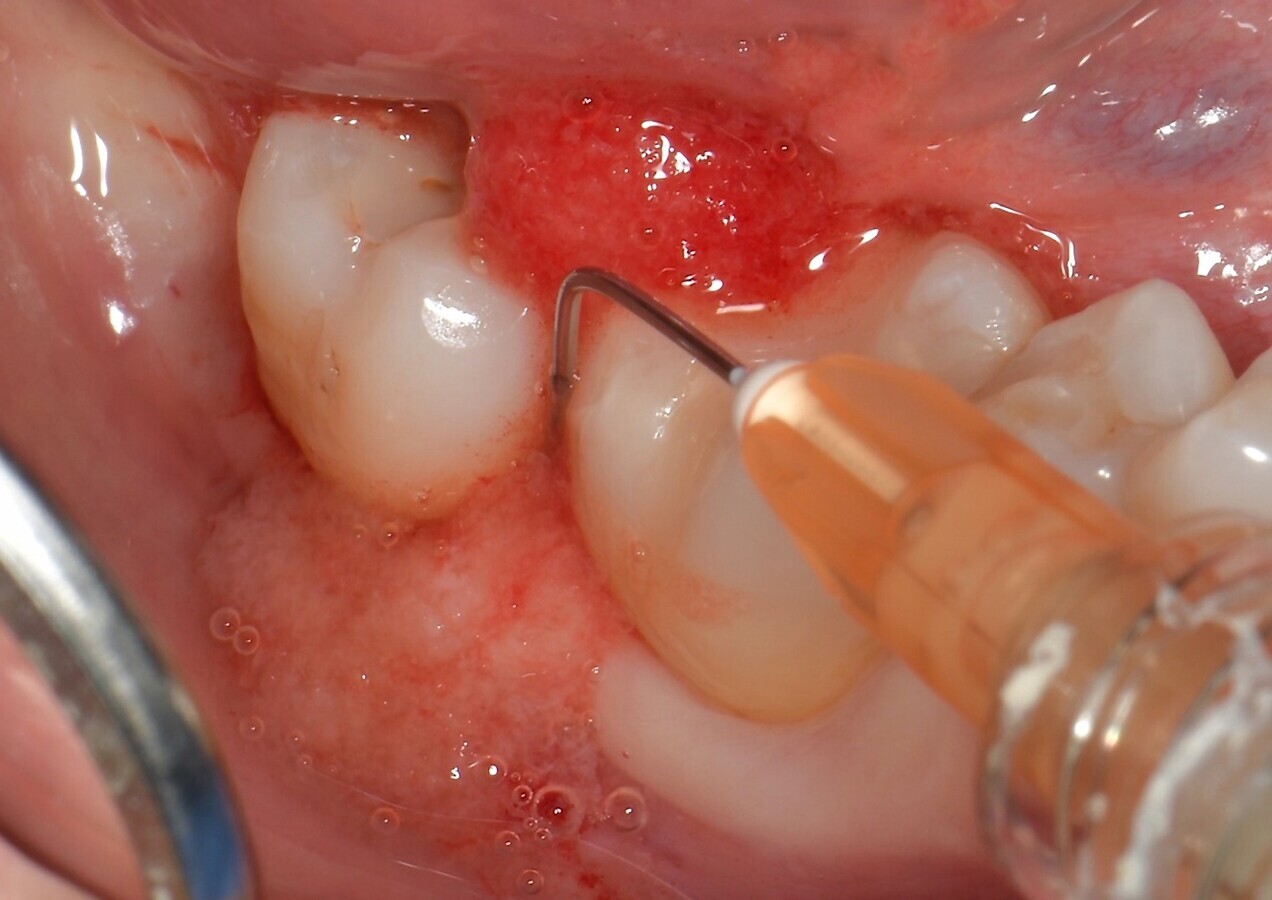

Todos los pacientes fueron sometidos inicialmente a raspado subgingival y alisado radicular utilizando insertos ultrasónicos específicos y curetas manuales. Posteriormente, las bolsas se rellenaron con un nuevo hidrogel de colágeno en una jeringa (H42, Bioteck Spa, Arcugnano - Vicenza) (Fig. 1) contiene colágeno tipo I, polímeros de alto peso molecular y cantidades auxiliares de vitamina C para optimizar la reología. El producto se aplicó utilizando agujas romas para irrigación de bolsas periodontales con Gauge entre 20 y 25, comenzando desde el fondo de la bolsa periodontal hasta que se llena por completo (Fig. 2).

Figura 2. El H42 se aplica desde el fondo de la bolsa periodontal hasta llenarla por completo.

Figura 5. Fase de fraguado del hidrogel de colágeno H42. La zona debe mantenerse seca durante 5 minutos tras la aplicación para favorecer la adhesión del tejido. El producto se coloca hasta llenar completamente la bolsa, hasta que rebalse.